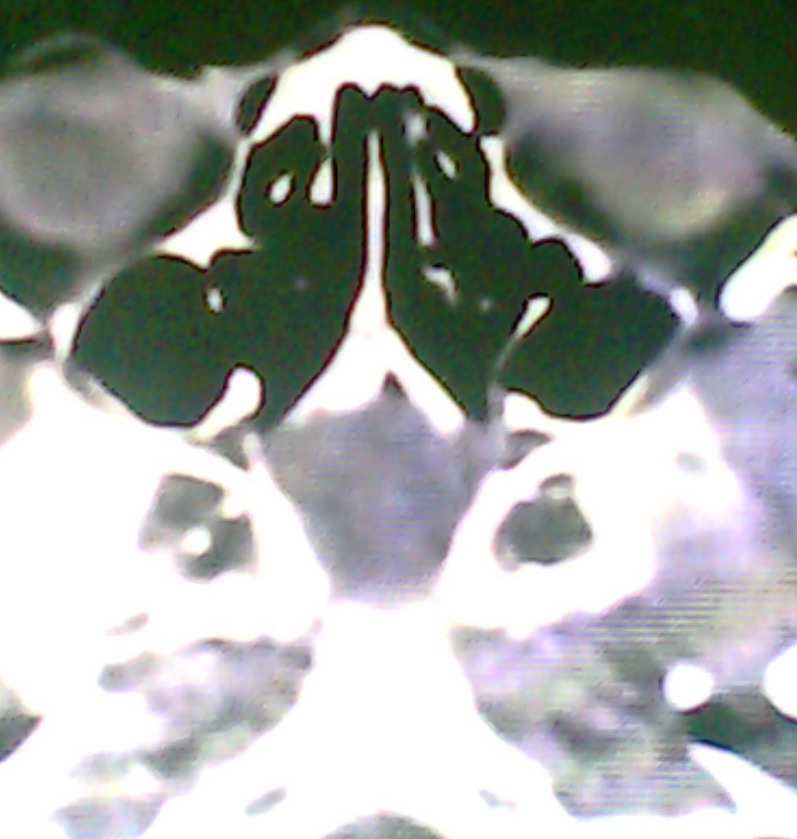

女、18岁,身高1.5左右,鼻塞、流涕数月,两侧瞳孔明显增大,曾与几年前去北京看眼,未发现病变。

考虑起源与蝶窦的粘液囊肿。

考虑脑膜脑脊液鼻内膨出

考虑起源于蝶窦的粘液囊肿突入鼻咽部。

\"几年前去北京看眼\"不知这句话有何玄机,支持考虑脑膜脑脊液鼻内膨出,膨出口在蝶鞍处

建议冠状面扫描,支持:脑膜鼻内膨出; 蝶窦粘液囊肿突入鼻腔可能性小。

在上级医院冠状位ct扫描后,诊断为:脑膜膨出,已住院准备手术。等待术后结果。